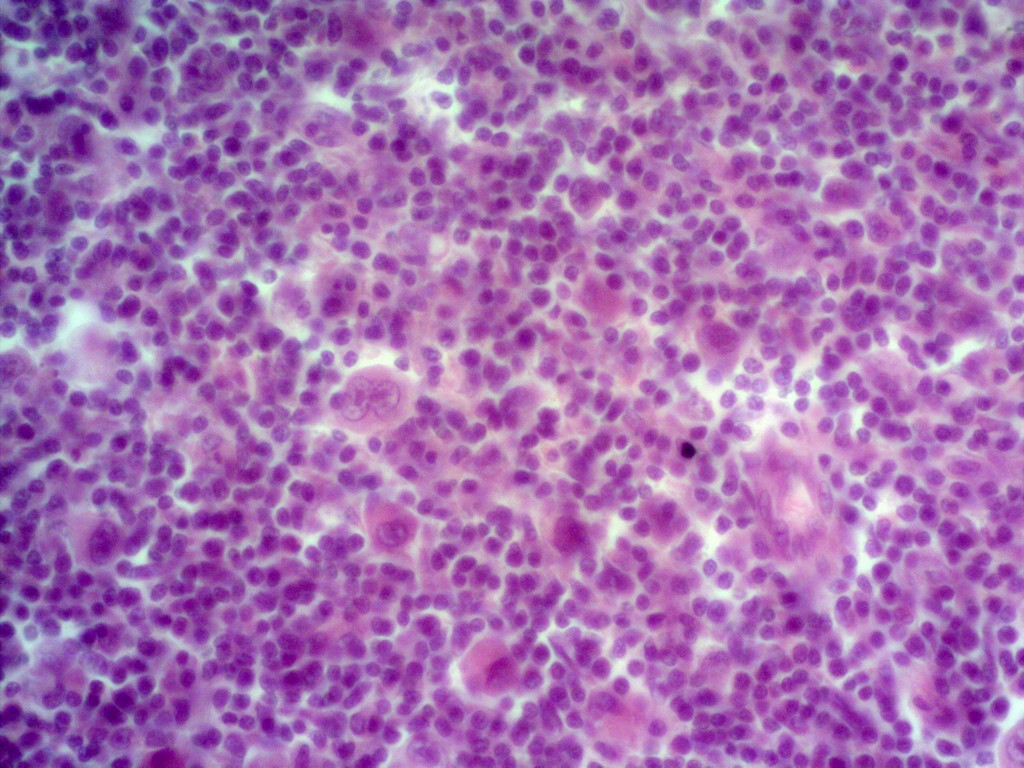

Микропрепараты: Лимфогранулематоз и Нодулярный Склероз